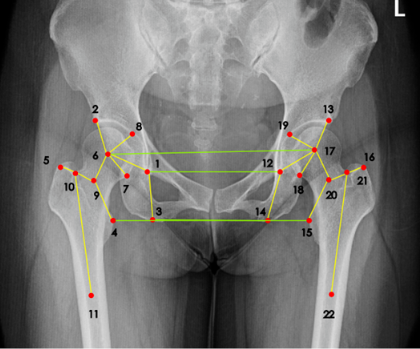

那么有没有可能通过某些自动化方法或者软件来完成准确而且标准的髋关节置换规划?答案是可行的。2018年左右,来自约翰霍普金斯大学的学者曾经提出通过两阶段卷积神经网络结构(CNN)来检测X射线成像图谱的手术测量标志点,并且能够从任意角度来完成成像检测。同时,也有有其他的一些研究试图引入人体解刨学特点,通过找到原本手术测量标志点之间的关系自动标注。但是在实践环节中,这些方法的准确率相较传统方案,并没有提升太多。

达摩院团队认为,医疗图像里不仅仅可以检测标志点,而且能同时自动学习这些手术测量标志点之间的关系,比如可以通过添加一个标志点的空间关系损失函数,来获得更加精确且高效的手术测量标志点检测结果。这种思想也就是把传统神经网络分别为两个支路:一个标志点预测分支,另一个边缘预测分支。在这种思想下,图像会先通过神经网络处理,再分别输入两个分支做不同目的的推理。其中标签预测分支将会把神经网络处理过后的高维特征转换为热点图,而边缘预测分支将会把神经网络处理过的边缘高维特征降维,此后向量化的标记将会提取更好的特征,这样可以通过一个专门针对标识空间位置建立的损失函数来提高边缘标签预测的准确度。